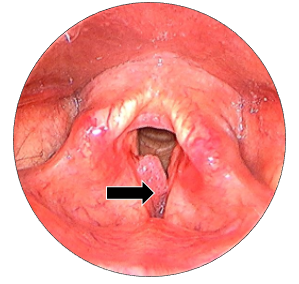

In suspension microlaryngoscopy (SML), (Figure 3) a Lindholm’s laryngoscope is used to expose the entire length of the vocal cords. External pressure can be exerted on the neck to improve the exposure of the anterior laryngeal commissure. The laser was operated using a micromanipulator coupled to an operational microscope. Using the CO2 laser set to ultrapulse mode, 100 mJ/cm2, 10 Hz repetition rate and and 250 m microspot, is used to resect the papilloma, thereby preserving the vocal ligament and normal mucosa at the anterior laryngeal commissure. The surgery is done around a small (6.5mm) endotracheal tube with the laryngoscope placed. Microlaryngoscopic view (Figure 4) showing papillomatous lesion over right true vocal fold. Following the mapping of the papillomas and photographs, cup forceps were used to obtain biopsies, which were then sent for regular pathology. Spot sizes of 0.5-0.8mm provide a comfortable compromise between depth of focus and cutting ability.

Figure 4 Microlaryngoscopic view of the true vocal folds. Black arrow: papillomatous lesion over right anterior 2/3rd aspect of vocal fold.